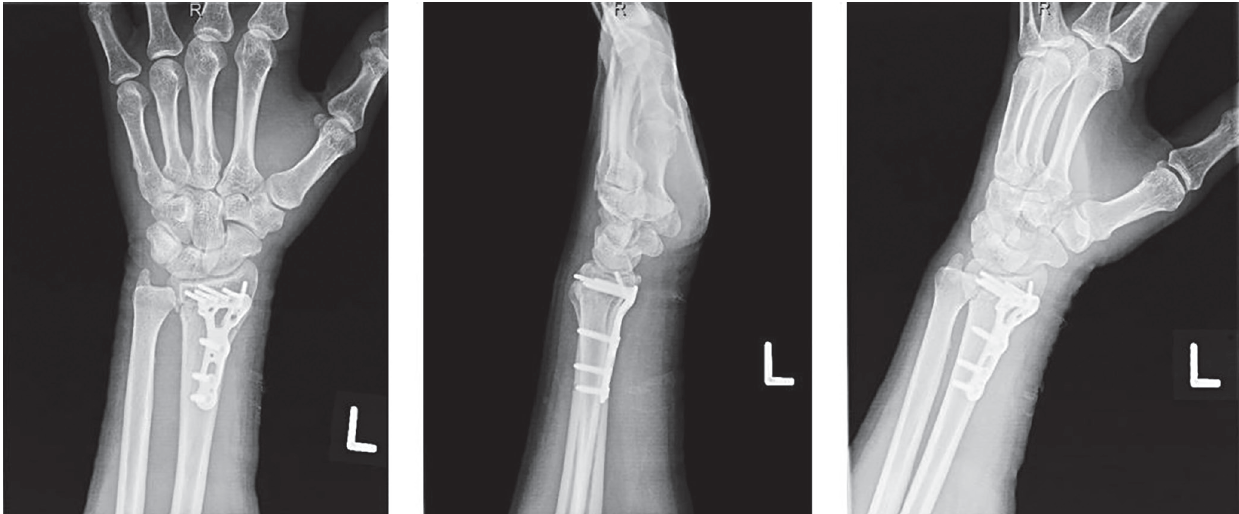

The patient tolerated the procedure well with no perioperative complications and was discharged the same day. Repeat radiographs obtained during the first postoperative clinic appointment several days later showed stable reduction with maintained alignment without hardware failure (Figure 3). Subjectively, the patient emphasized feeling great relief postoperatively with respect to markedly decreased numbness and tingling along the ulnar nerve distribution and reported slight improvement in sensation along the median and ulnar nerve distributions. Hand-specific occupational therapy was begun on postoperative day 2 with the assistance of a specialized therapist. The patient continues to improve and follows up regularly in clinic.